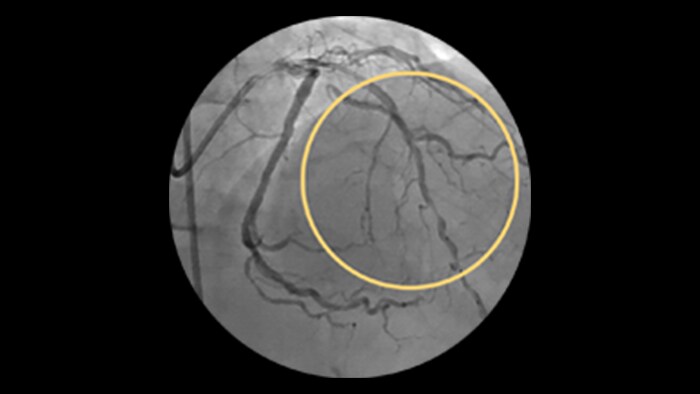

Calcified Lesions

An increasing number of patients with calcified coronary artery lesions are being referred for PCI. A recent pooled analysis reported moderate to severe target lesion calcification in 32% of patients.1

Advanced tools for optimal PCI outcomes